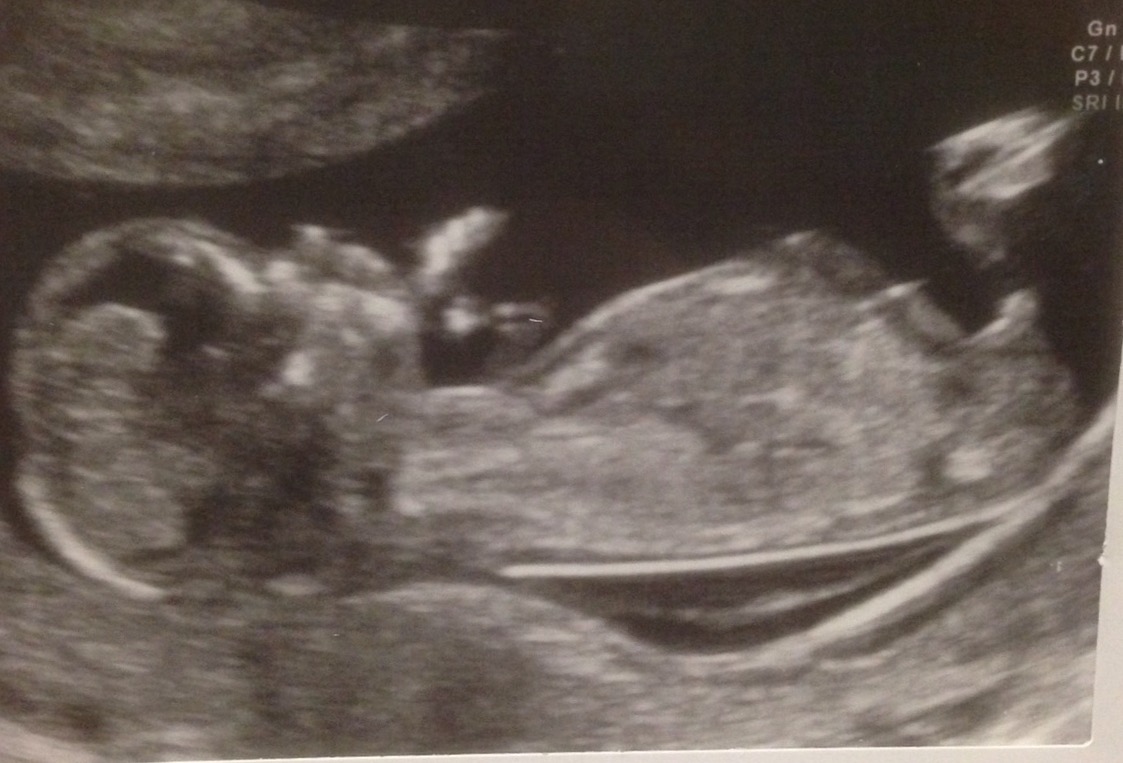

Boy bits or cord please help guys

Perfect boy nub

I'm thinking boy